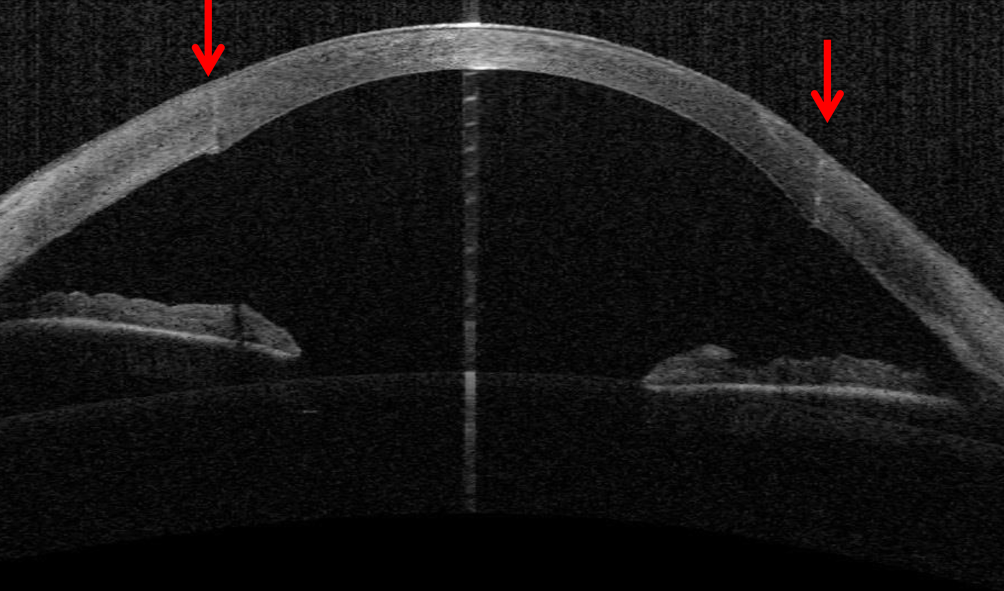

Die intrastromalen Hornhautimplantate stellen eine elegante und effektive Option dar, um den unkorrigierten und bestkorrigierten Visus zu verbessern und (wie durch ein „Korsett“) auch die Progression des Keratokonus einzudämmen (Abb. 9a, b). In einer Langzeitstudie mit einem Follow-up von im Mittel 3 Jahren zeigten nur 2,7 % der Patienten unter 35 Jahre eine Progredienz des KK nach reiner INTACS-Implantation [57]. Nichtsdestoweniger ist prinzipiell eine Kombinationstherapie mit CXL möglich – besonders bei jüngeren Patienten mit stärkerer Progressionstendenz. Vor allem Patienten mit einer Intoleranz gegenüber formstabilen Kontaktlinsen profitieren von dem abflachenden – also hyperopisierenden – Effekt der intrastromalen Hornhautimplantate, sodass oftmals bei „regularisiertem Astigmatismus“ wieder eine Brillen- oder Kontaktlinsenanpassung möglich wird.

Abb. 9

Intrastromale Hornhautimplantate stellen eine elegante und effektive Option dar, um bei mäßiggradigem Keratokonus die Hornhautverkrümmung abzuflachen und zu regularisieren und so den unkorrigierten und bestkorrigierten Visus zu verbessern. a Spaltlampenübersicht. b Die beiden ovalären Polymethylmethacrylat(PMMA)-Ringsegmente liegen symmetrisch in 80 % Tiefe der Hornhaut (VA[Vorderabschnitt]-OCT [optische Kohärenztomographie])

Voraussetzung für die Implantation von ICRS sind eine Hornhautdicke von > 450 µm in der 6‑ bis 7‑mm-Implantationszone der Vorderabschnitts-OCT und eine narbenfreie optische Zone. Die zentrale Hornhautdicke spielt hierbei eher eine untergeordnete Rolle. Die Lage, Dicke und Geometrie der Halbringe wird individuell entsprechend dem Nomogramm der Herstellerfirma angepasst.